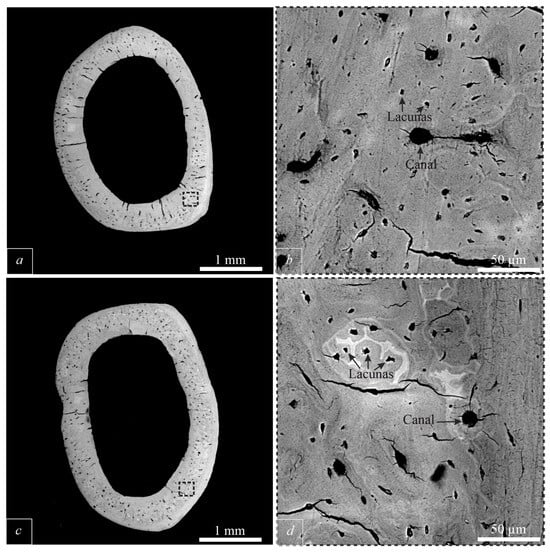

3.1. Micromorphology of Bone Tissue and Chemical Composition of BA

3.2. Bone Tissue Ultrastructure and Structural Characteristics of BA